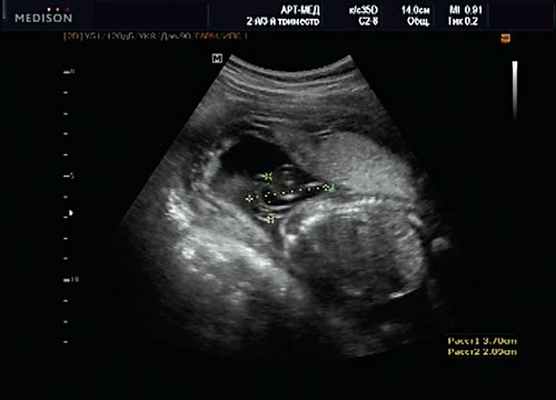

Клиническое наблюдение 3

Беременная 27 лет, обратилась в клинику в 18 нед. При эхографии обнаружен синдром Арнольда - Киари II, умеренно выраженная гидроцефалия (рис. 17).

В крестцовом отделе позвоночника выявлена spina bifida cysticа (рис. 18).